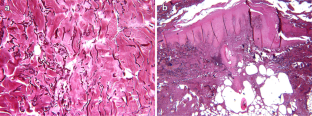

Bariatric surgery is the most effective treatment for morbid obesity. Despite this, side effects are recorded. One of them is redundant skin hanging from the patients’ body causing both aesthetical and functional deformities. They can only be corrected with body contouring surgery, whose wound complication rate is very high in previously obese population. Despite several hypotheses, an adequate explanation is still awaited. The aim of our study was to evaluate the wound healing process in post-bariatric patients. Seven patients, six women and one man, were enrolled. They all were nonsmokers and nondiabetic. They all underwent biliopancreatic diversion (BPD). After 36 months, abdominoplasty was performed. Biochemical parameters before and after bariatric surgery were evaluated. The content of total protein and hydroxyproline was assessed in multiple scar biopsies before and after BPD. Abdominoplasty horizontal scar skin samples were subjected to histological evaluation with Weigert–Van Gieson stain for elastic fibers and connectivum. All biochemical parameters analyzed were reduced post-BPD compared to the preoperative period. Tissue proteins were significantly reduced after BPD both in their totality and as hydroxyproline and hydroxyproline/total tissue protein. Histological evaluation revealed abnormal dermal elastic and collagen fibers. The cause of aberrant healing in massive weight loss body contouring is likely multifactorial. A relationship between nutritional state, wound collagen accumulation, and elastic fiber content seems to be only partially involved. The high mechanical stress of tissues before BPD probably influences the wound healing process after BPD.

Fig. 1

Fig. 2